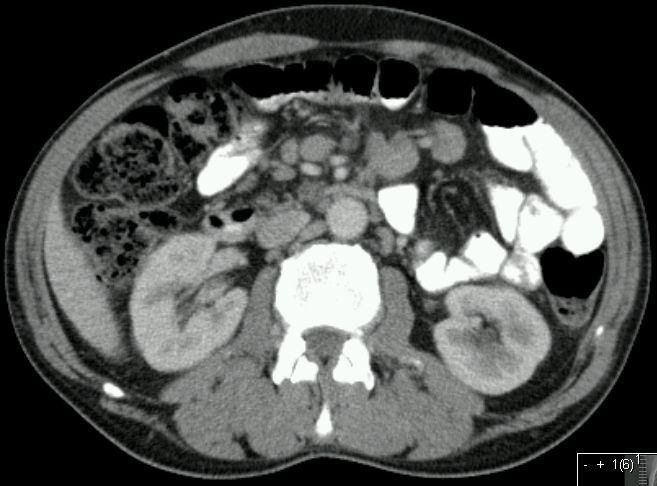

T3 N2 M1

65-jähriger Mann mit fortgeschrittenem Peniskarzinom. Glans und Corpus callosus befallen.

inguinale Lymphknotenmetastasen gut sichtbar.

symmetrische inguinale Metastasen